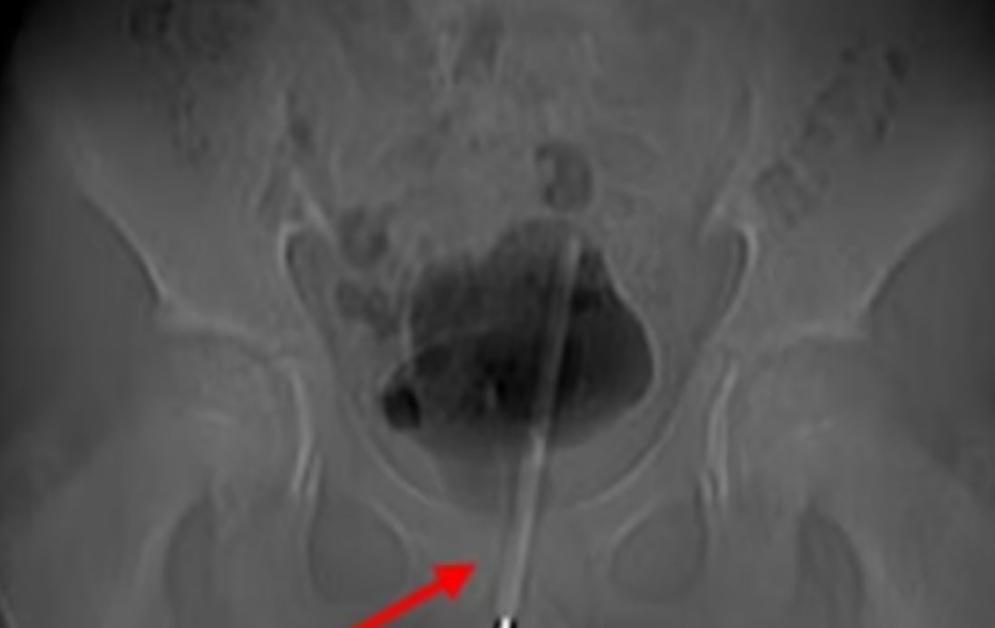

Un băiat de 12 ani și-a introdus un termometru pe penis, însă, de rușine, a așteptat 9 ore până când s-a hotărât să ceară ajutor. Radiografiile făcute de medici au arătat că instrumentul medical a fost introdus atât de adânc în tractul urinar încât intrase în vezica băiatului.

A suferit dureri crunte timp de nouă ore până când a cerut ajutorul, fiind rușinat că incidentul a avut loc în timp ce se satisfăcea singur. Radiografiile făcute de medici au arătat că instrumentul medical a fost introdus atât de adânc în tractul urinar încât intrase în vezica băiatului, potrivit Daily Mail.

Doctorii au făcut o mică incizie în țesutul vezicii urinare și apoi au introdus instrumente minuscule pentru a manipula termometrul în unghiul și poziția corectă pentru a-l scoate din coprul băiatului. Din fericire, au reușit să scoată termometrul, operația fiind un succes.